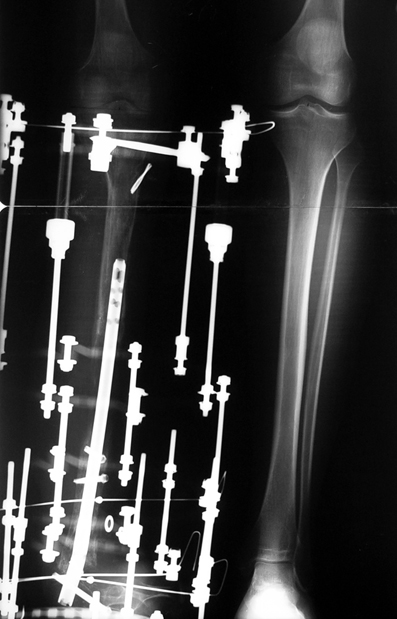

3. POSTTRAUMATIC LOWER LIMB SHORTNESS (MALUNION)

This type of shortness occurs after a fracture heals in a shortened position. Most cases are seen in adults and can be treated with one lengthening operation. Additional deformities can be corrected simultaneously. Most of these cases can be treated with lengthening over nail or just corrections and intramedullary nailing.